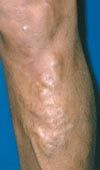

Chronic venous insufficiency. This is characterized by edema, lipodermatosclerosis, stasis dermatitis, and healed or active venous ulcerations. In patients with lipodermatosclerosis, the skin may initially have a pinkish hue (Figure 3), which becomes progressively darker. Eventually, a brownish discoloration develops (Figure 4). Stasis dermatitis, or stasis eczema, is an exacerbation of this process (Figure 5). This inflammatory reaction must be distinguished from cellulitis, because antibiotics are not effective in treating stasis dermatitis.